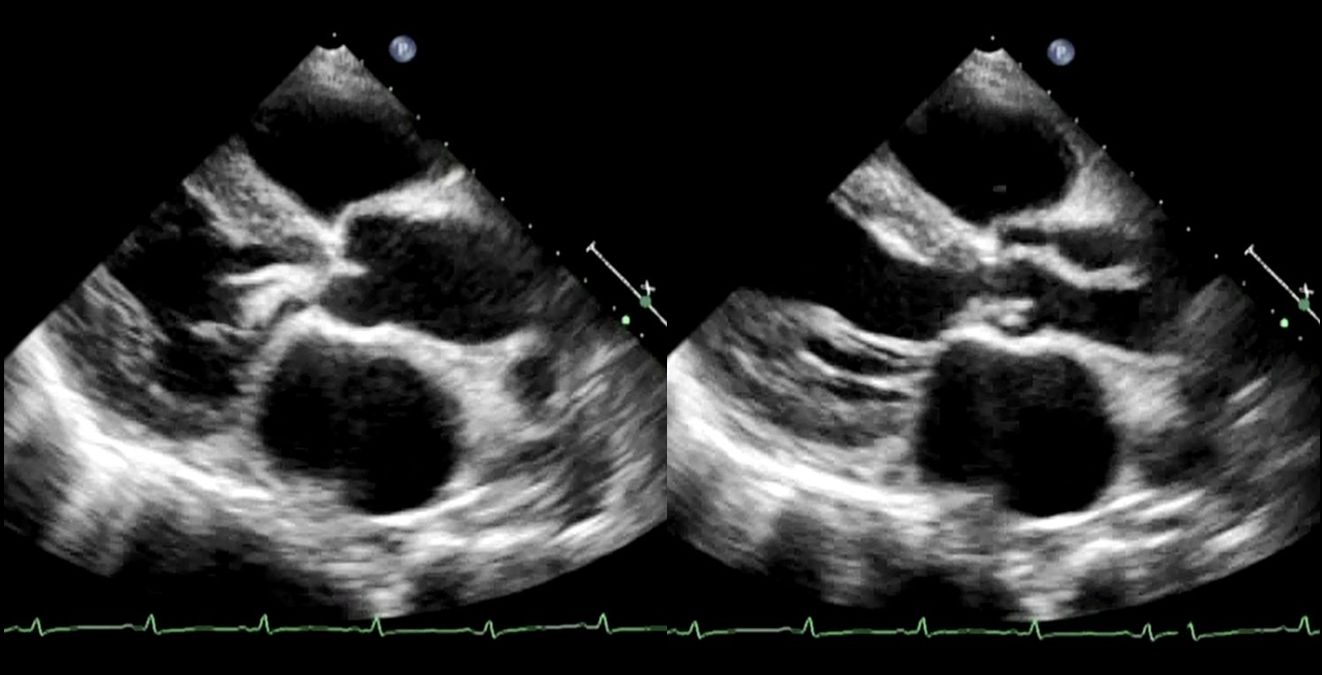

感染性心内膜炎